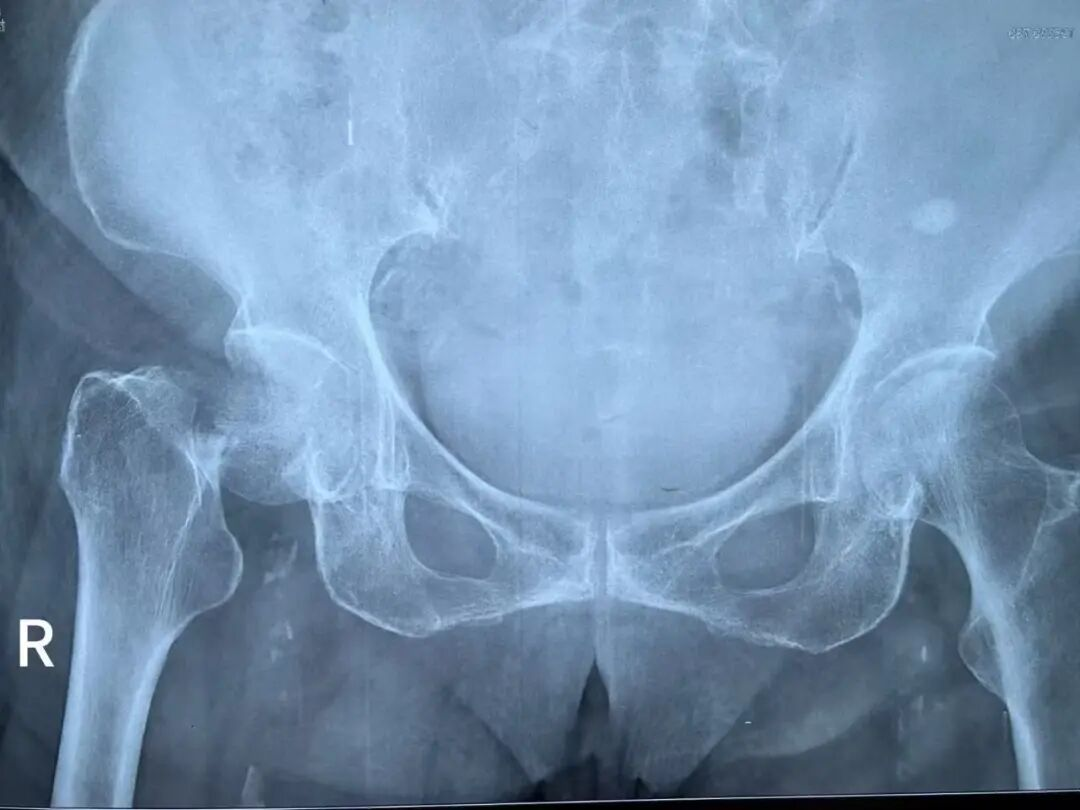

1月15日晚9点,青岛西海岸第二医院关节外科单彬副主任接诊了一位因在家中摔倒导致右髋关节疼痛伴活动受限的86岁高龄患者。经诊断,患者为右侧股骨颈骨折—这是老年群体中被称为“人生最后一次骨折”的高危损伤,常因各种并发症危及生命。

关节外科单彬主治医师提前定制围手术期快速康复(ERAS)管理方案,优化术前、术中和术后处理措施,实现快速康复、缩短住院时间、降低并发症发生率和再入院风险;并结合影像学检查(术前影像显示股骨颈移位明显),联合李阳副主任医师共同制定手术方案,确定实施右髋人工股骨头置换术,以最小创伤实现快速康复。麻醉科全面评估老人心肺功能,量身定制个体化麻醉方案,通过精准用药提前控制血压、血糖及心律失常,将麻醉风险降到最低;心内科全程深度参与,指导围手术期心血管用药,积极转复心律,实时监测心脏功能,为手术期间的循环稳定保驾护航。

(术前影像)